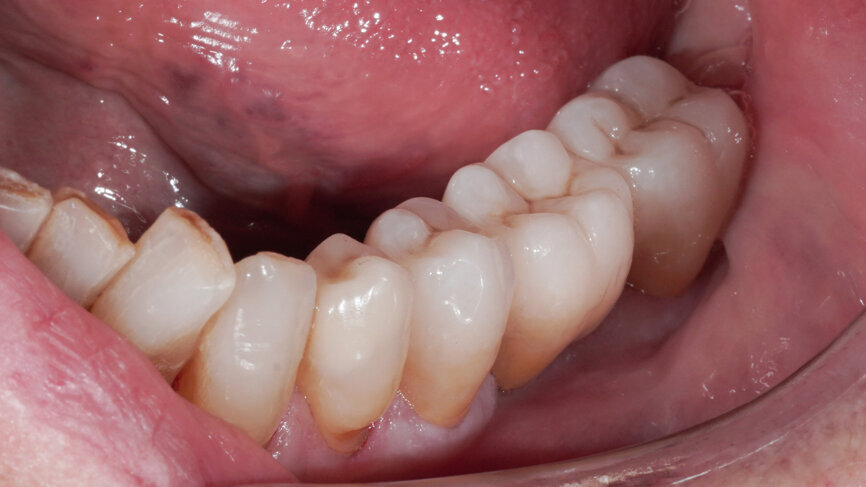

Fig. 11: Clinical situation after restoring the teeth with a lithium disilicate onlay and a zirconia bridge.

Fig. 12: Clinical situation after restoring the teeth with a lithium disilicate onlay and a zirconia bridge.